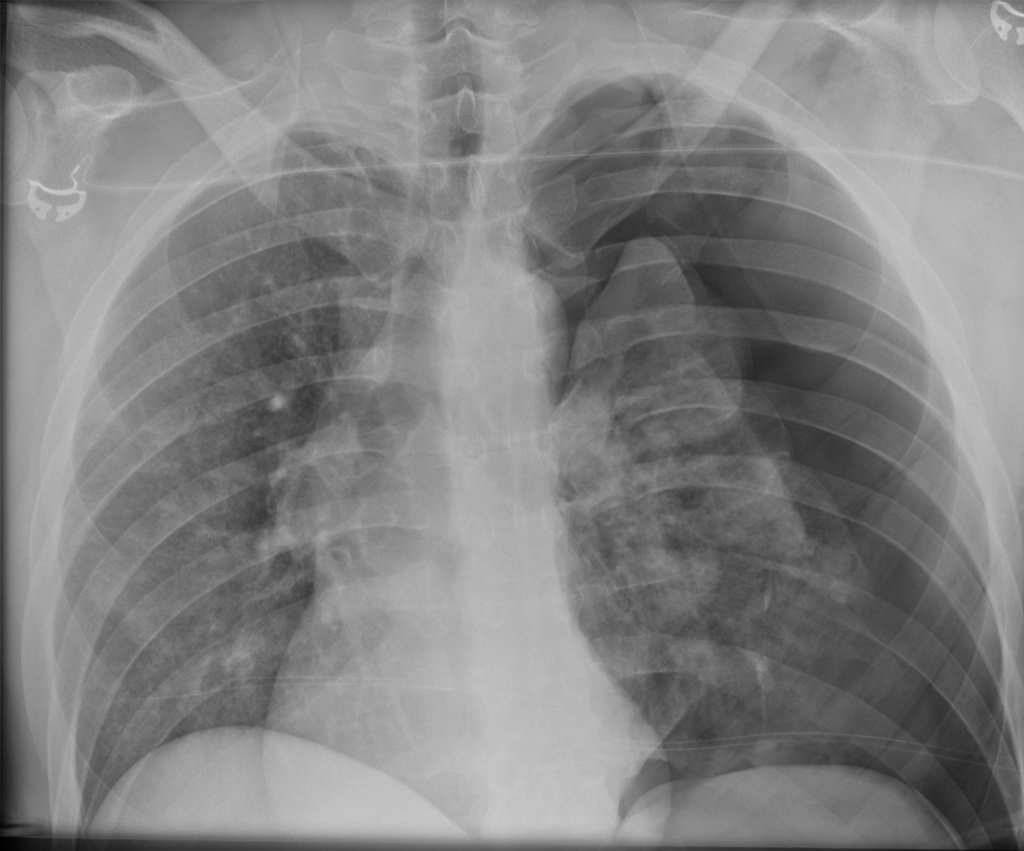

Examination findings in pneumothorax

Pneumothorax vs pleural effusion?

Pleural effusion occurs more slowly and is dull on percussion

Pneumothorax occurs rapidly and is hyperresonant on percussion